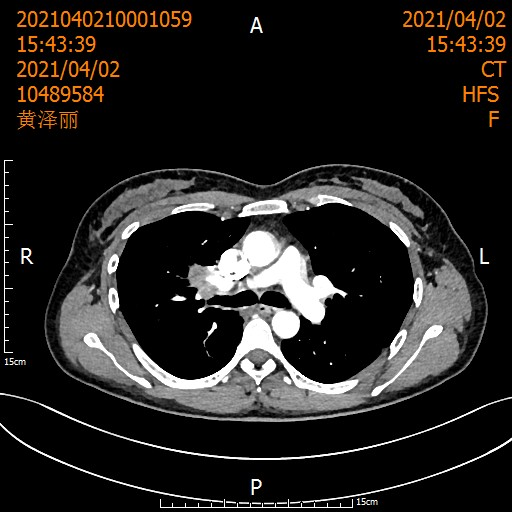

遵循《国际专家共识》,刘浩团队启动了术前2周期化疗联合3周期"卡瑞利珠单抗+紫杉醇/卡铂"治疗。

治疗后患者影像